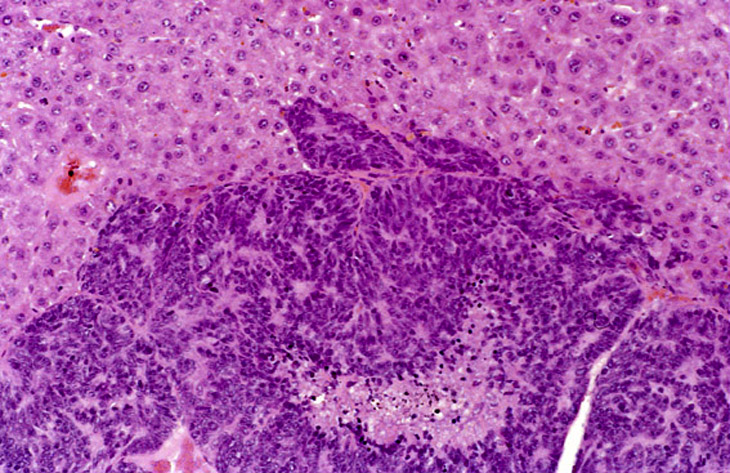

A large hepatoblastoma; higher magnification shows malignant cells palisading around vascular structures.